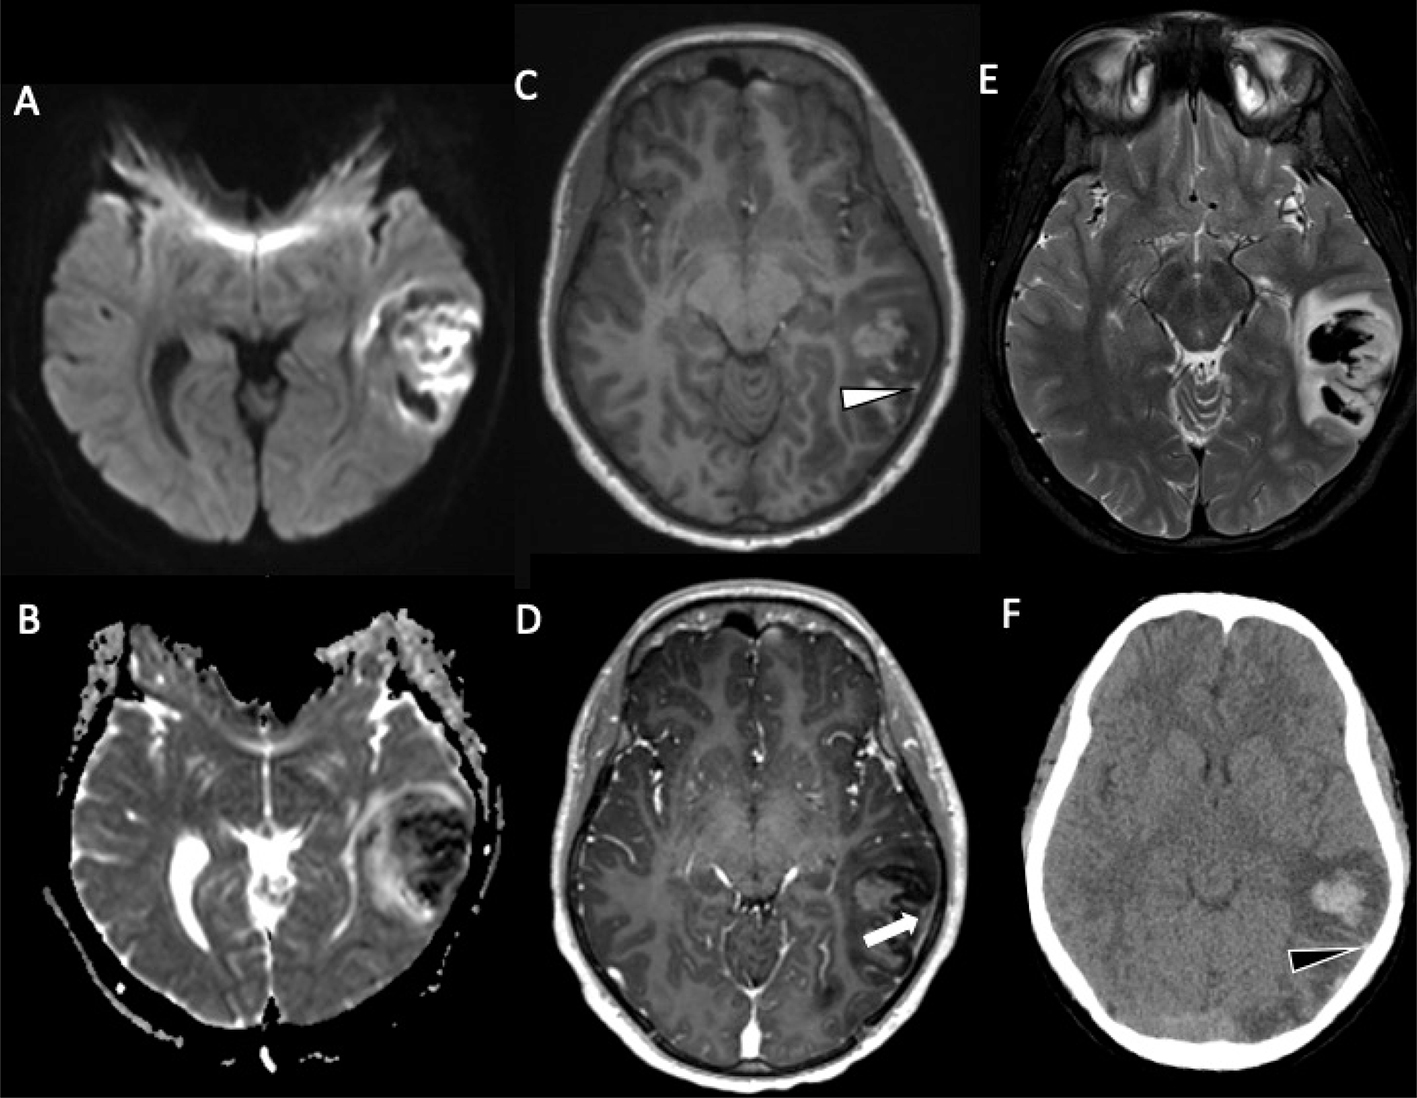

Focal cerebral arteriopathy (FCA), also known as transient cerebral arteriopathy, is a common cause of pediatric AIS in previously healthy children (Figure 1) (16, 17, 2124). Defined by an acute, monophasic illness causing unilateral stenosis of the intracranial cerebral arteries, mainly involving the anterior circulation, FCA was found in 36% of children presenting with acute stroke in one series (23). FCA can be further subdivided into the following subtypes: FCA– dissection type (FCA-d), FCA–inflammatory type (FCA-i), primary and secondary Moyamoya disease, genetic or syndromic arteriopathies (such as PHACE syndrome), vasculitis, fibromuscular dysplasia, and iatrogenic forms (Figures 2) (25, 26). The appropriate diagnosis is important to establish because prognosis can be improved by treatment of the inflammation, when present. FAC-i is associated with viral infection and vaccination may reduce the incidence (16, 17, 24, 27). Varicella zoster virus (VZV) is an established cause of FCA, although other pathogens, including other herpes viruses, likely play a role as FCA continues to occur in VZV vaccinated children (16, 28, 29). Age of onset differs between arteriopathy subtypes, with FCA-i tending to affect older school-aged children, Moyamoya affecting younger children, and dissection generally presenting no age predilection (30). COVID-19 has been reported as a cause of FCA, also resulting stroke related to the prothrombotic effects leading to AIS and venous sinus thrombosis (3133). Inherited vasculopathies include, such as mutation in ACTA2, with distinctive imaging features which may suggest such diagnoses (34). Disorders of coagulation may be identified, including deficiencies of proteins C and S, G20210A prothrombin mutations, and factor V Leiden, as well as the presence of anticardiolipin antibodies (19, 3538). In patients with no underlying metabolic disorders, trauma and previous viral infection are significantly more common (16, 17, 39, 40). Genetic or acquired conditions causing thrombophilia are less common causes (41).

Fig 1

Figure 1. A six-month-old male who presented with acute right hemiparesis. DWI (A) demonstrates acute infarct in the left basal ganglia and deep white matter (white arrow). MRA (B) shows severe stenosis of the left M1 middle cerebral artery segment (black arrow). Follow-up 4 months later, demonstrates evolution of the infarct, now with encephalomalacia and gliosis without new acute infarct (white arrowhead) (C). MRA at that times shows mild improvement but persistent MCA stenosis (black arrowhead) (D). Findings are most compatible with focal cerebral arteriopathy.

MRA can help define the site of stenosis, helping narrow the diagnosis in patients with arteriopathy, or identify a large vessel occlusion (Figure 4) (17, 23, 95, 96). A “banding” pattern is considered a pathognomonic feature for FCA-i but is less commonly identified by CTA or MRA than catheter angiography, presenting in less than one-quarter of cases, and is therefore specific but not sensitive for the diagnosis (Figure 5) (30). If arteriopathy is suspected and MRA is equivocal, vessel wall imaging, utilizing black-blood, T1-weighted volumetric imaging after gadolinium can demonstrate abnormal vessel wall enhancement in the setting of active inflammatory processes, as well as assess for intracranial arterial dissection on pre-contrast T1-weighted imaging (69). Between 64% and 74% of arterial defects in pediatric ischemic infarctions are located in the supraclinoid carotid artery or M1 segment of the middle cerebral artery (70). Stenosis in FCA may change in appearance over the short term. Over the long term, they usually normalize (~25%), stabilize after improvement (32%), or stabilize (45%) without further infarctions (23, 24). Outcome is better in patients in whom the arteriopathy stabilizes or improves than in those in whom it progresses, with a high risk of recurrent stroke in the latter population, approaching 25% within 1 year (17, 24). Some genetic arteriopathies have unique imaging appearances, such as ACTA2 mutation, which demonstrates dilation of the proximal internal carotid arteries, occlusion or narrowing of the distal internal carotid arteries, straight “broomstick-like” arteries of the circle of Willis, and absence of lenticulostriate collaterals (Figure 6) (34).

Fig 4

Figure 4. A 19-year-old female with a history of Down syndrome and repaired ASD and VSD. The patient presented with 2 days of aphasia, alerted mental status, and right upper quadrant field cut. Axial CT (A) demonstrates hypoattenuation with loss of gray-white differentiation in the left middle cerebral artery territory (black circle). DWI (B) and corresponding ADC (C) confirm acute left MCA territory infarct (white circle). MRA (D) demonstrates focal left MCA M2/M3 occlusion (arrow). She was found to be positive for Lupus anticoagulant.

Fig 5

Figure 5. A 13-year-old previously healthy female who presented with new left-sided facial weakness. Diffusion weighted image (A) demonstrate acute infarcts in the right middle cerebral artery (MCA) territory (black arrows). Time-of-Flight MRA (B) shows stenosis of the proximal right M1 MCA segment (white arrowhead). Vessel wall imaging (C) demonstrates a cuff of enhancement at the stenosis (white arrow). Digital subtraction angiography (D) demonstrates a focal arterial irregularity and banding (black arrowhead) resulting in mild stenosis, compatible with focal arteriopathy of a likely inflammatory nature.

Fig 6

Figure 6. ACTA2 Mutation. Axial ADC (A) demonstrates reduced diffusivity in the periventricular white matter, compatible with acute infarct. 3D Time-of-Flight MRA (B) shows enlargement of the internal carotid arteries (arrowheads) with narrowing of the distal internal carotid arteries (arrow). Follow-up axial T2-weighted image (C) shows evolution of the infarct to cystic encephalomalacia. Case courtesy of Dr. Tamara Feygin, Department of Radiology, Children’s Hospital of Philadelphia.